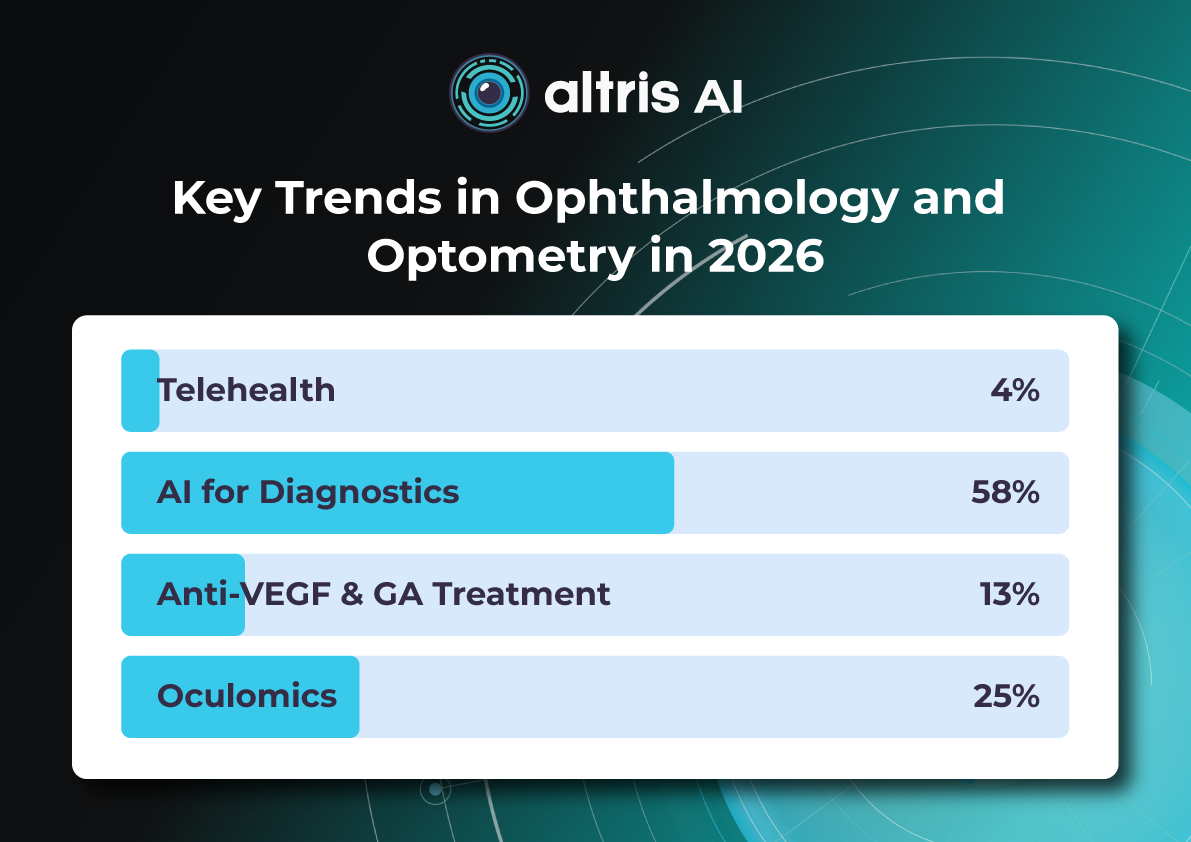

For this article, we surveyed eye care professionals on which optometry technology appears most promising to them. The answers were divided among AI for more precise diagnostics, advanced contact lenses, and new iterations of OCTs.

Of course, this is not the whole list of possible new tech in optometry, but these are the topics that draw the most attention today.

The article delves deeper into each of these technologies, as well as explores oculomics, the new way of understanding the correlation between eye pathology and overall human health.

AI has blossomed in recent years, transforming not only how we work and relax but also how we manage our health. It’s no surprise that our survey of professionals revealed AI as the most promising technology in optometry.

Optometry Technology: Oculomics

For decades, researchers have sought to measure retinal changes to identify ocular biomarkers for systemic diseases, a field now known as oculomics.

The link between the eye and overall human health is not new. However, with the increasing availability and complexity of large, multimodal ocular image datasets, artificial intelligence-based ocular image analysis shows great promise as a noninvasive tool for predicting various systemic diseases. This is achieved by evaluating risk factors, retinal features, and biomarkers. Thanks to the massive datasets generated through recent ophthalmic imaging, which are now being used for deep learning and AI training, oculomics is starting to yield more precise answers. For example, the NHS alone has been conducting eye tests for over 60 years, resulting in databases containing millions of images, complete with patient records and long-term health outcomes. These datasets have been fed into AI algorithms, leading to models that can already predict cardiovascular risk factors with accuracy comparable to the current state-of-the-art methods.